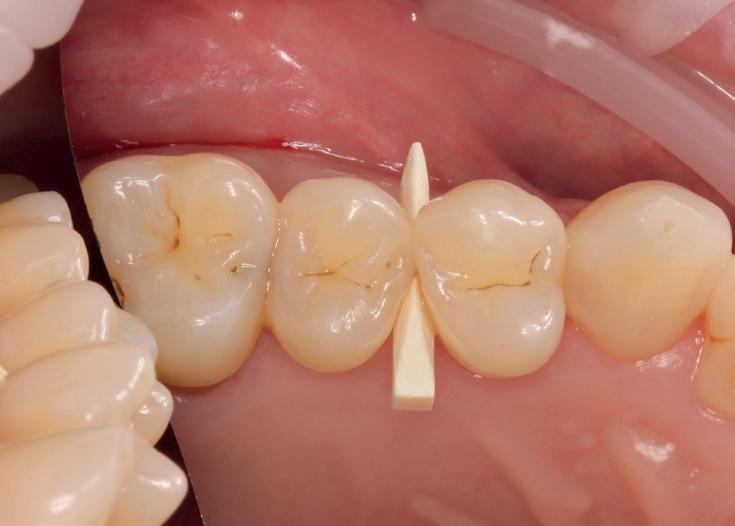

De OptraGate (mondspreider) werd aangebracht en na het geven van de lokaalanesthesie werd het element cariësvrij gemaakt. Een interdentale wig werd Na de preparatie werd er een matrixstrip tussen wig en element geplaatst zonder extra separatieklem. Doordat de preparatieranden netjes vrij liggen van het

buurelement is plaatsen ervan simpel. De voorgevormde matrix volgt de contour van het te restaureren element nauwkeurig. Door de wig in situ te laten of net een beetje van zijn plaats te halen voor het plaatsen van de matrix ontstaat er geen of nauwelijks bloeding uit de gingiva.

Met dentalfloss worden de randen altijd op overhang gecontroleerd en tot slot worden storingen in occlusie en articulatie verholpen. Door in het begin al een goede vormgeving te realiseren beperkt zich dit tot een minimum.

Met een vlamvormige diamant wordt de geringe buccale en palatinale overmaat verwijderd. Dit is goed mogelijk doordat de preparatie randen vrij liggen van het buurelement. Cervicaal wordt een scherpe scaler gebruikt om de geringe overmaat voorzichtig te verwijderen met een naar cervicaal gerichte beweging. Doordat er eerst een dunne laag flowable is uitgehard op de cervicale outline en opstaande wanden is deze overmaat overigens minimaal en makkelijker te verwijderen dan composiet! Het steviger composiet bevindt zich occlusaal waar de kauwkrachten moeten worden weerstaan.

Er is een vereenvoudigde anatomie aangebracht zonder staintechniek en secundaire/tertiaire fissuren. Het contactpunt is goed hersteld en de randen zijn goed te inspecteren. De optische integratie voldoet goed. De getoonde restauratie werd in 15 minuten voltooid. Diepere restauratie randen en grotere caviteiten kunnen met dezelfde methode worden behandeld, doch zullen meer tijd in beslag nemen.

Een separatiering is dus met deze getoonde methode zeker niet altijd per se nodig om een goed contactpunt of goede vorm en randaansluiting te verkrijgen. De toepassing van flowable maakt in dit verband bij diepe cervicale randen een “margin elevation” mogelijk. Je hoogt als het ware eerst de boxbodem wat op (zie gele lijn in

tekening) waarna opnieuw een matrix in een hogere positie kan worden geplaatst.

Door het vrijleggen van de preparatieranden is goede afwerking immers altijd mogelijk. Soms belemmert een ring juist het goed plaatsen en modelleren van het composiet. De initiële laag flowable voorkomt doorpersen van het stugge composiet en als er overmaat ontstaat, is het flowable composiet gemakkelijk weg te halen met een dunne finier, mesje of tandsteensintrument. Auteur geeft de voorkeur aan doorzichtige matrixstrips zodat altijd goed te zien is wat je doet. De getoonde matrix is van de firma Hawe Neos (Adapt Sectional matrix). Omdat met een ‘wet bonding techniek’ (Adhese Universal) kan worden gewerkt is relatieve isolatie met een OptraGate in deze casus voldoende. Cofferdam is hier dus niet per se nodig. Het gebruik van vereenvoudigde anatomie scheelt extra werktijd. In de esthetische zone kan het wel een meerwaarde bieden zoals onderstaande restauratie in de 46 laat zien. Het betreft een DOL composiet restauratie. (i.v.m. afgebroken distolinguale knobbel van dit element)